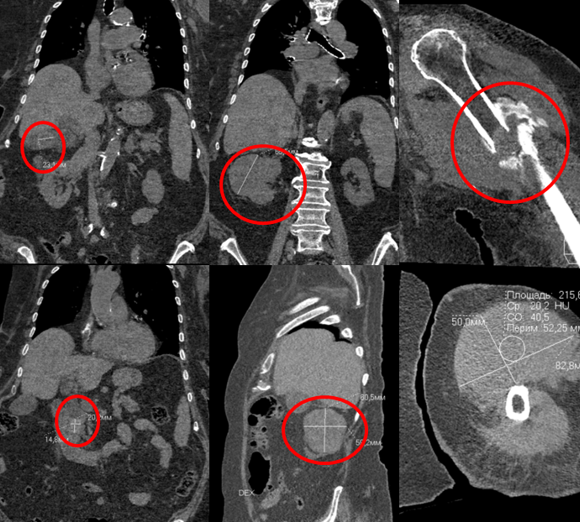

92-летняя женщина обратилась к рентгенологам Центра Илизарова с жалобами на сильные боли в плечевом суставе на фоне перелома плечевой кости.

Обследование на ультрасовременном оборудовании показало помимо перелома плечевой кости – образование в почке, камни холедоха и желчного пузыря.

- Велика вероятность, что перелом плечевой кости был патологическим на фоне метастатического поражения. Результаты обследования позволяют нам предполагать, что у пациентки рак почки, - рассказал заведующий рентгеновским отделением Центра Илизарова, д.м.н. Константин Дьячков.